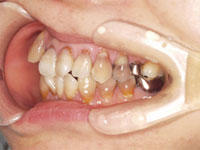

歯の奥が腫れてだんだん痛くなってきた患者様の症例

吉本歯科医院では、口内写真とパノラマレントゲンを撮影し、まずは顎の骨の状態まで詳しく確認しました。

口内写真.

院長の吉本の診断は、以下の2つでした。

・虫歯の進行により、歯の根っこに膿が出来てしまった

・咬み合わせが悪いことにより、虫歯になりやすい(バイ菌がたまりやすい)